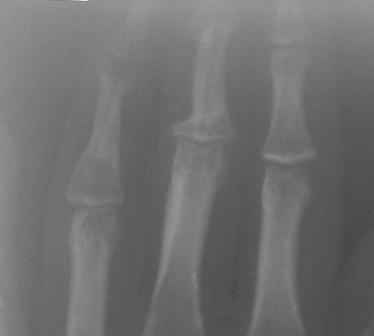

[Ortho] Непонятный процесс в основной фаланге пальца

Уважаемый Юрий, действительно, онкологи делали пункционную биопсию.

Конечно, мы во время операции будем брать материал на гистологию, а

также удаление очага и  замещение аутотрансплантатом тоже в плане

правда снимки не очень качественные, прощу извинения!